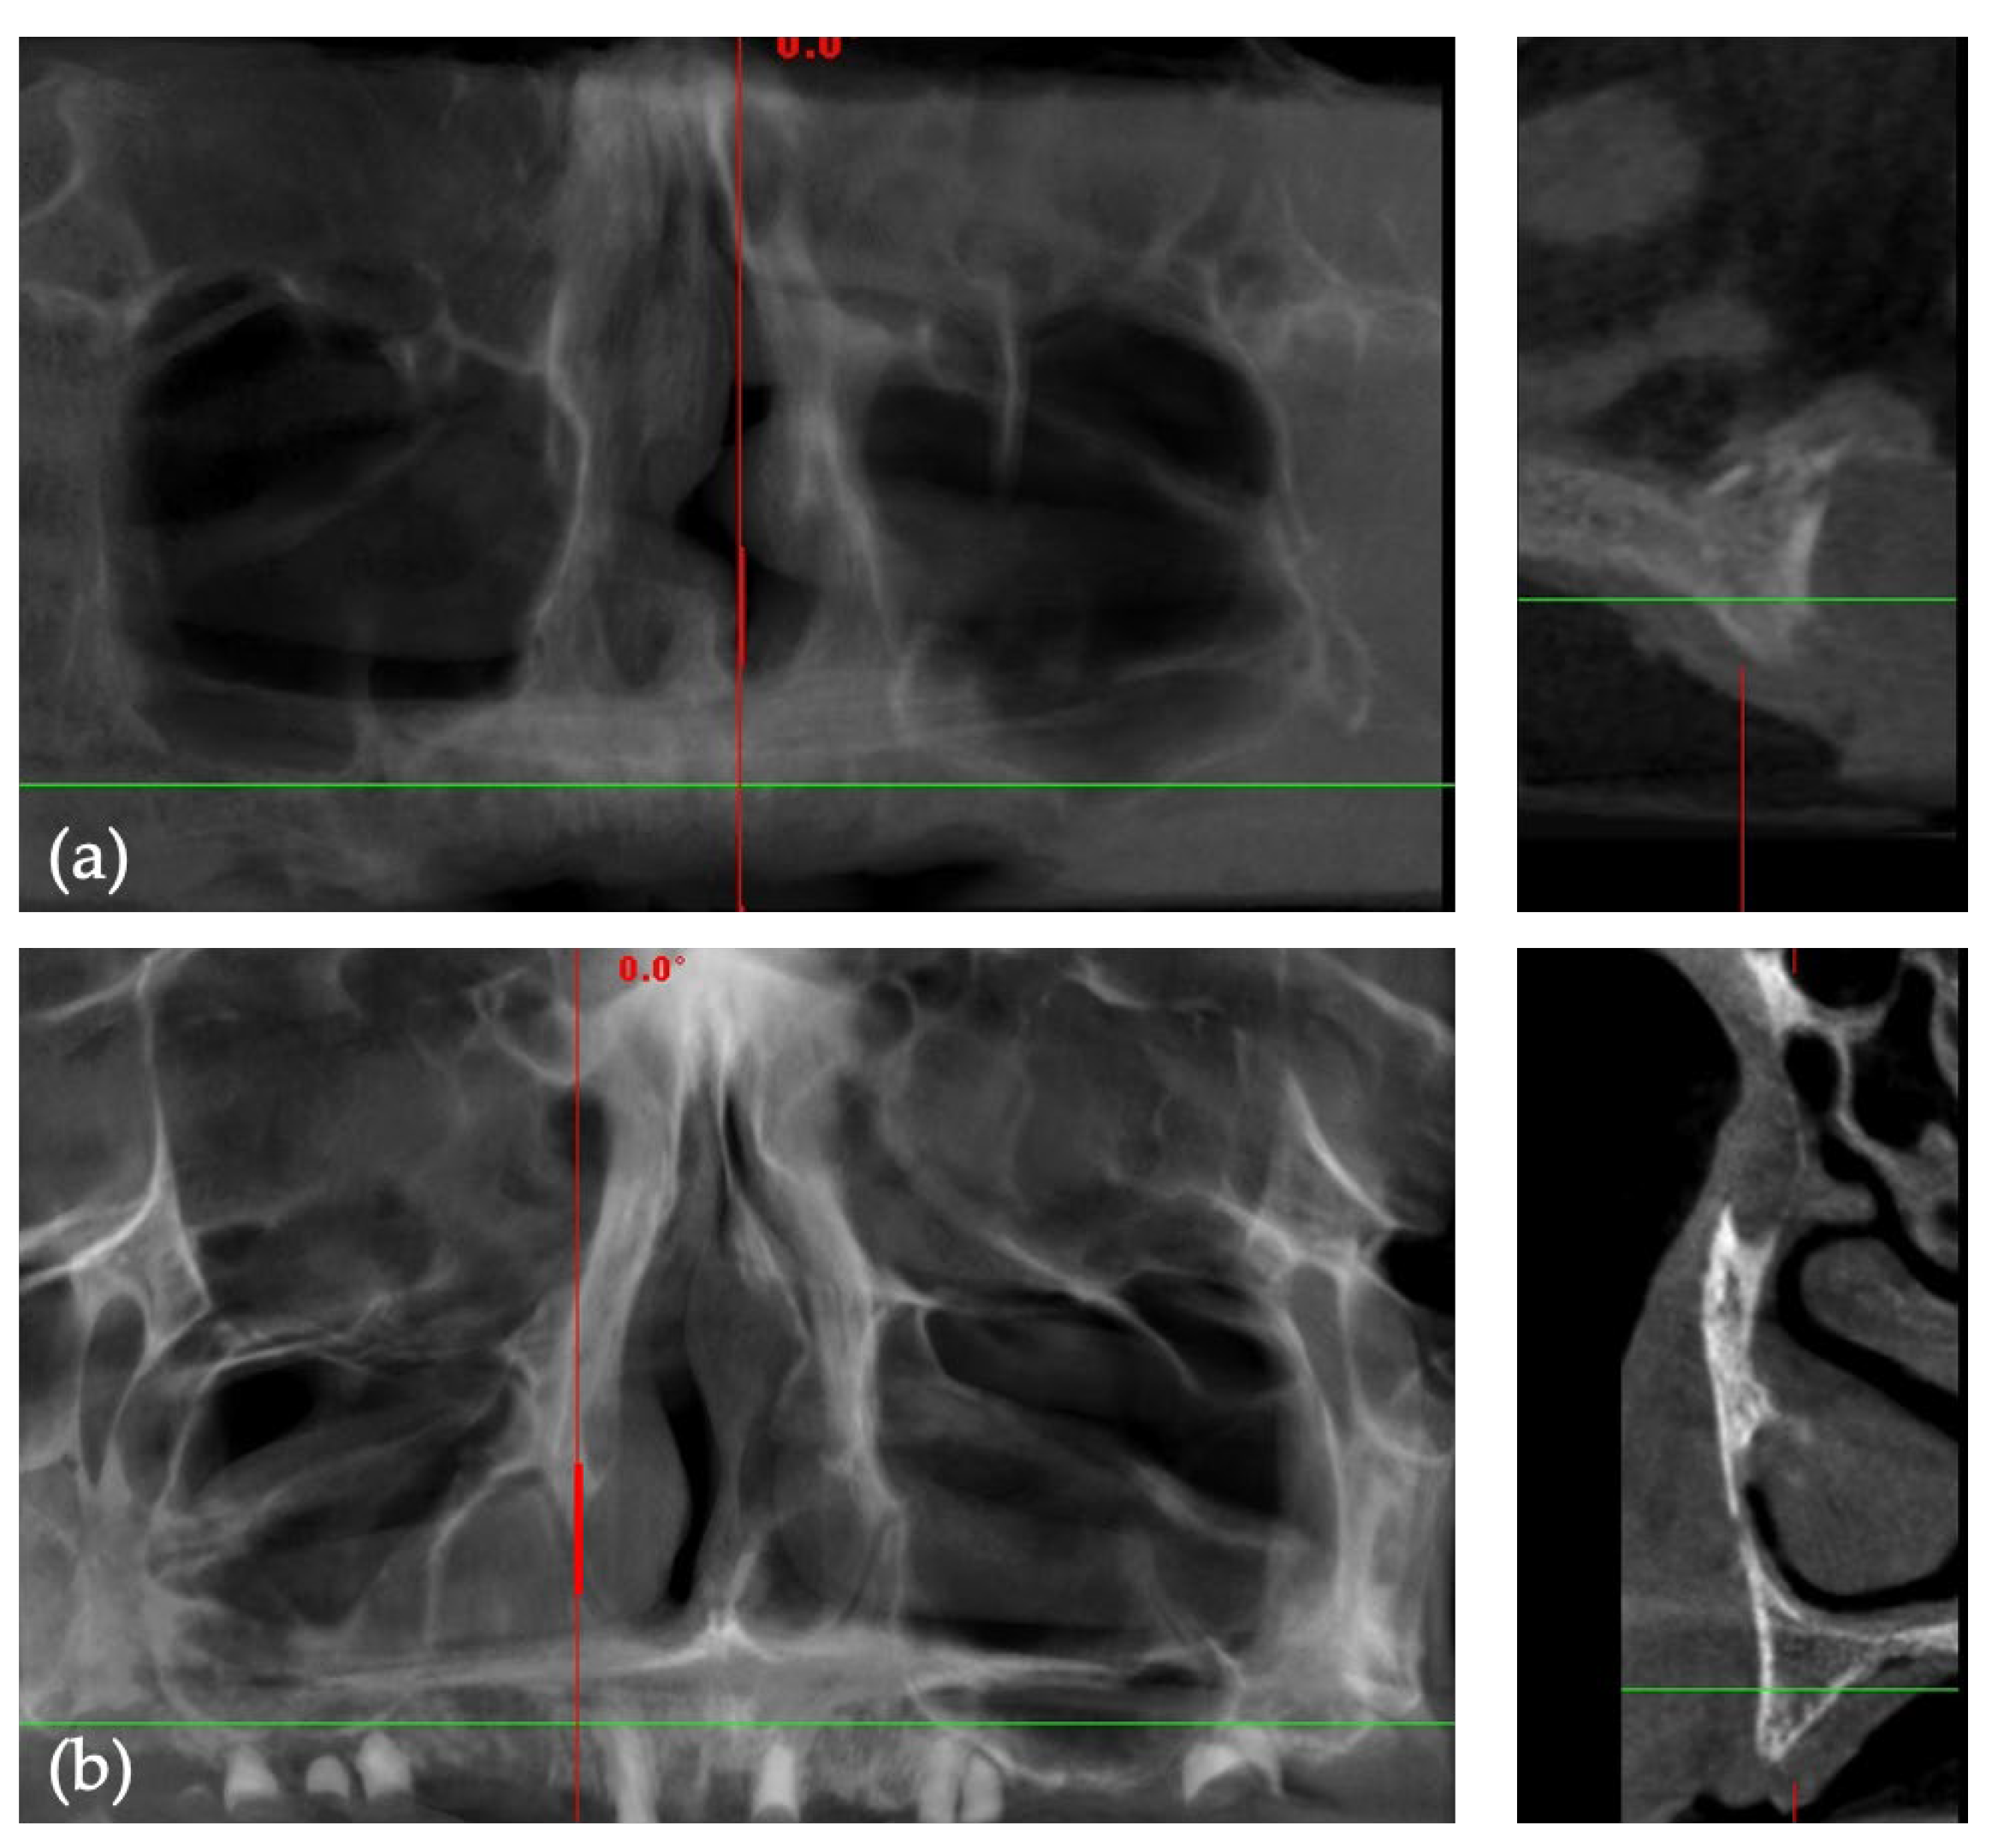

2.2. Pre-Surgical Cone-Beam Computed Tomography (CBCT)